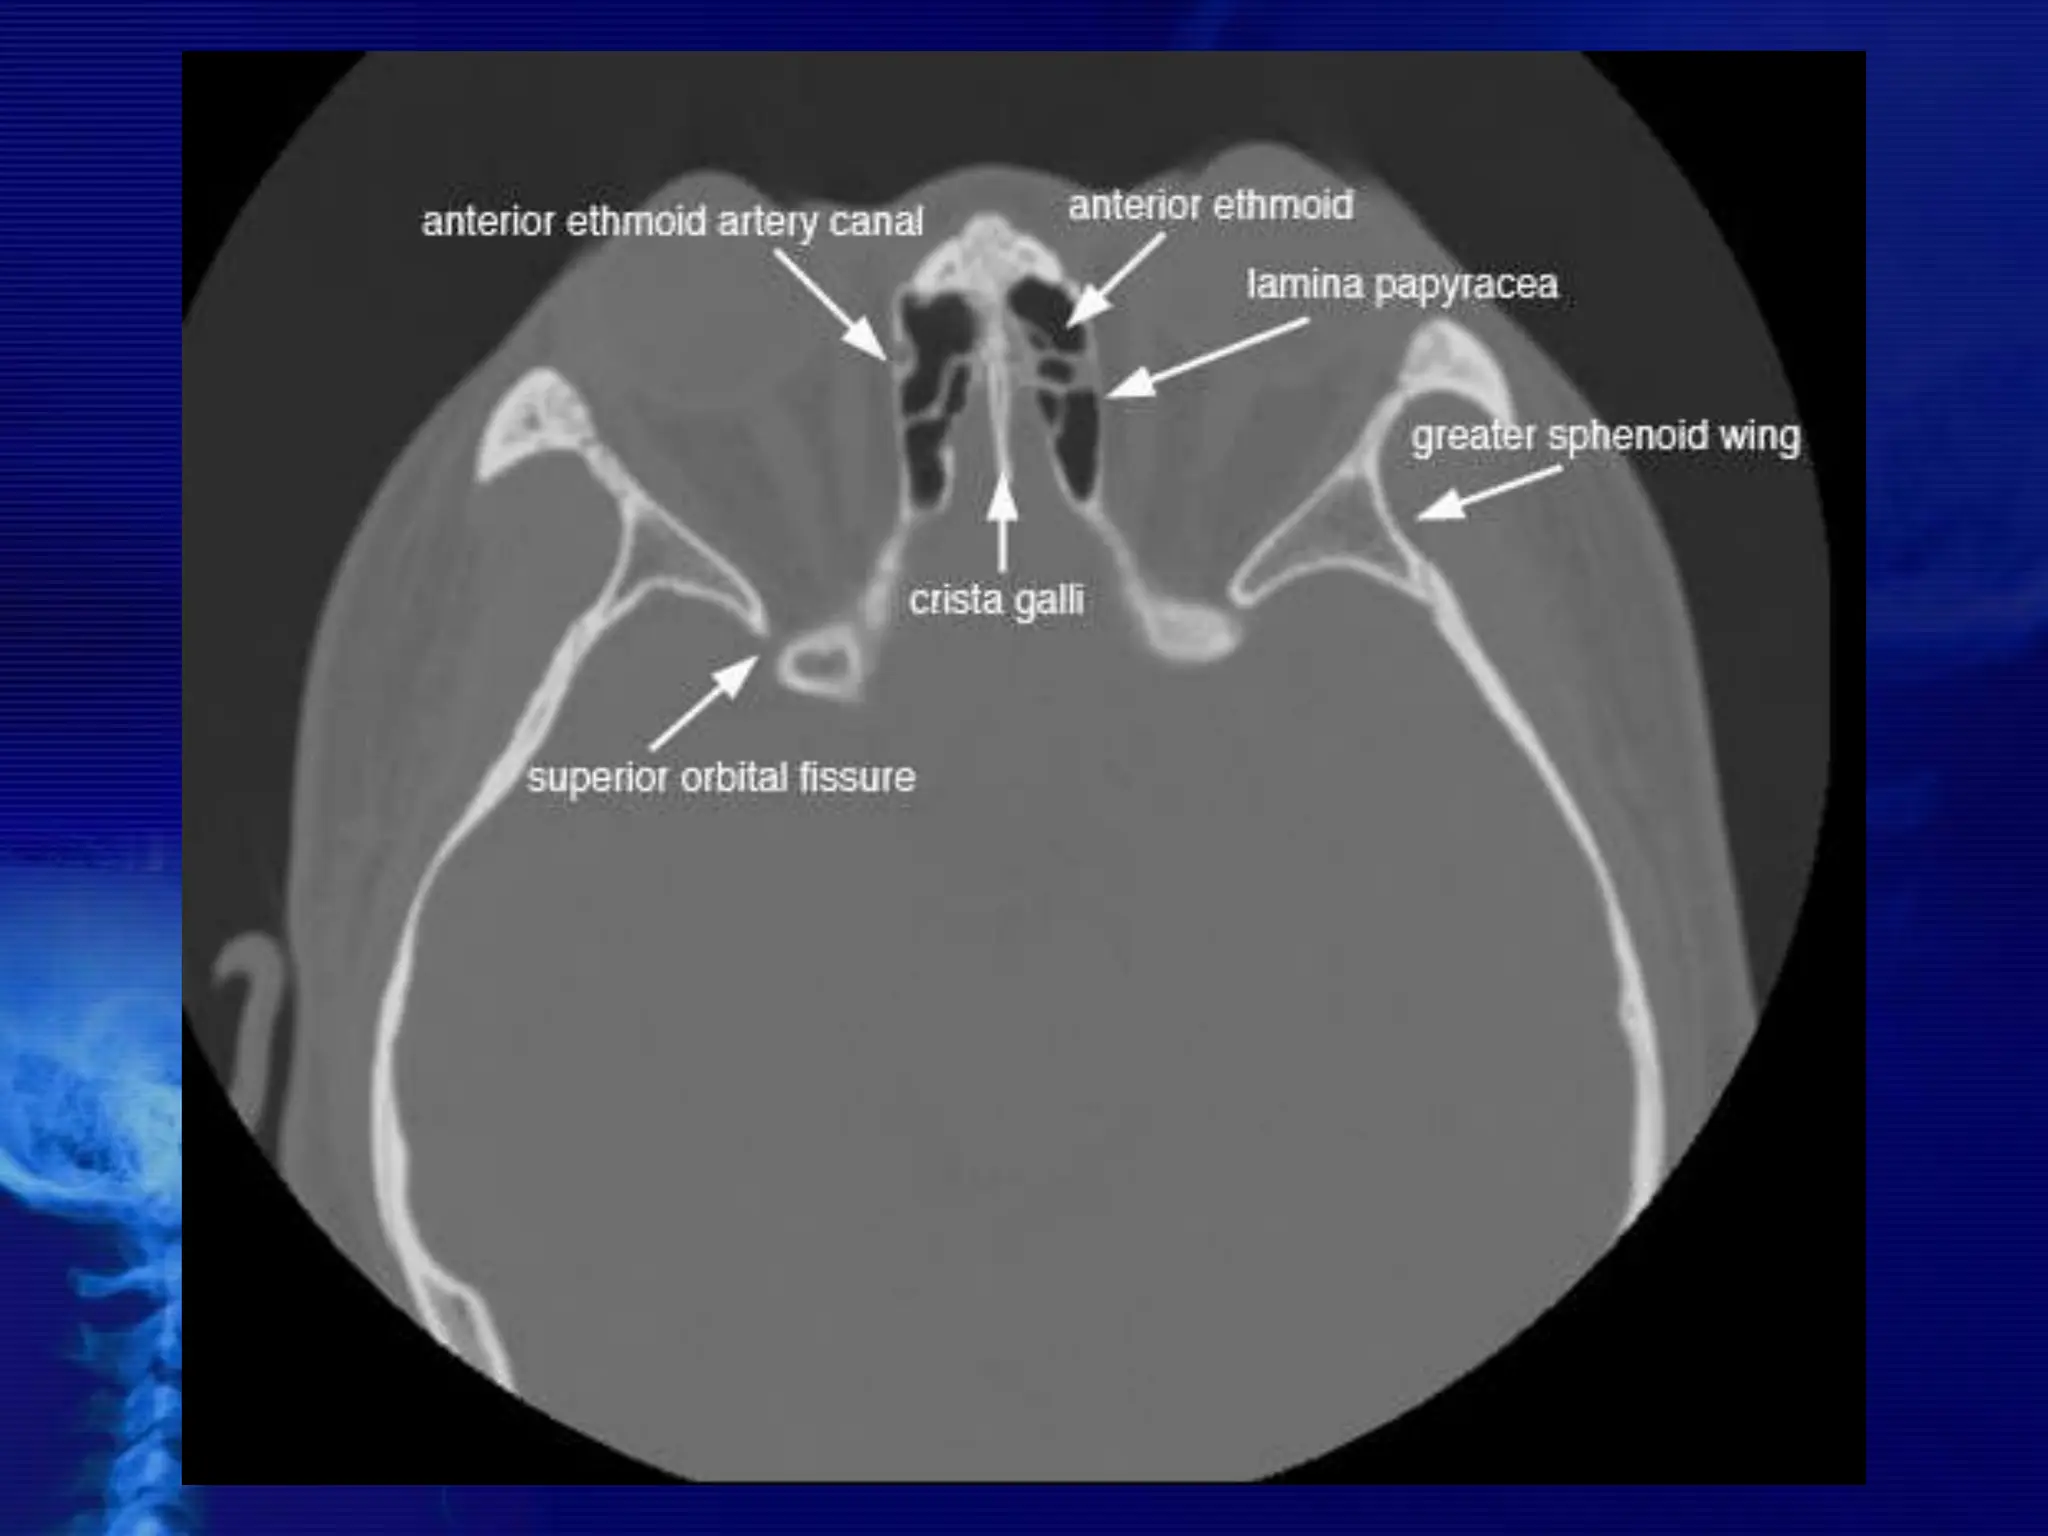

CROSS SECTIONAL ANATOMY –

AXIALS

BASIC CONCEPTS • CTscans typically obtained for visualizing the paranasal sinus should include coronal and axial (3- mm) cross sections.  Soft tissue and bony windows facilitate evaluation of disease processes and the bony architecture.  The use of intravenous contrast material just prior to scanning can help define soft tissue lesions and delineate vascularized structures, such as vascular tumors.  Contrast-enhanced CT is particularly useful in evaluating neoplastic, chronic, and inflammatory processes.

 The CTscan is the GOLD STANDARD investigation in all preoperative cases as it gives detailed bony anatomy of the area and serves as a ‘road map’ for the operating surgeon.  CT scans are best done after a course of antibiotics, so that acute inflammation is not mistaken for chronic mucosal disease.